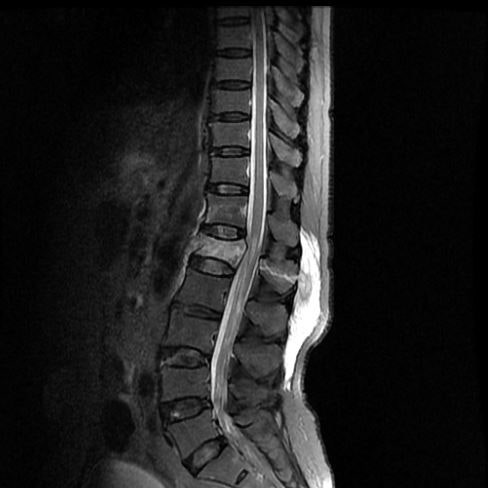

요추의 1번 부위는 흉추의 후만과 요추의 전만이 교차하기에 외부의 큰 충격을 받게 되면 취약할 수 밖에 없는 부위입니다. 대다수 추락사고, 낙상사고, 교통사고 등 다양한 이유로 요추1번 골절 진단받아 일반적으로 TLSO 보조기 착용하시며 보존적 치료 진행하시는데요, 일반적인** 폐쇄성 압박골절**이 아닌 척추체가 터지듯 골절되는 방출성골절, 또는 신경 손상등의 우려가 있을 때 골절된 척추체의 위 아래뼈도 함께 고정하는 척추 유합술(고정술) 까지 시행합니다.